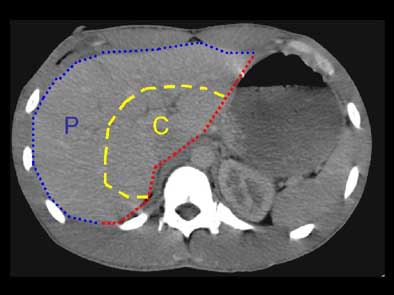

"This (division) is arbitrary, but the central area of the liver we took to represent the hilum, the area where the main bile ducts and blood vessels are coming through, and tried to distinguish that from the peripheral aspects of the liver," Lucey said. "We also decided whether the liver lacerations extended to the medial or lateral edge of the liver, or both. All active bile leaks were documented on HIDA scans.

| The liver was divided into sections for the study. The red line represents the medial surface of the liver. The blue line represents the peripheral surface (P) of the liver. The yellow line roughly separates the peripheral from the central part (C) of the liver. All images courtesy of Dr. Brian Lucey. |

"The reason this is important is that it means you can have a laceration involving the medial and lateral surfaces, but it will remain a peripheral laceration rather than extending to the central portion of the liver," he said.